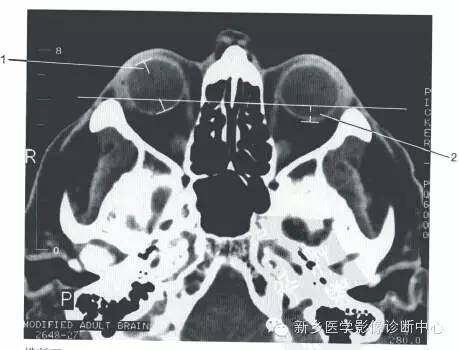

眼眶的正常数据